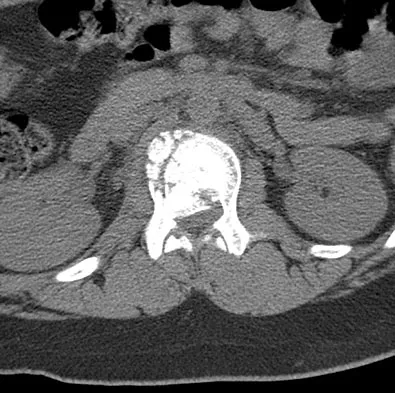

Figure 7 shows the CT scan of a 25-year-old soccer player who has had posterior ankle pain with plantar flexion for the past 2 years. Immobilization has failed to provide relief. He is ambulatory. Management should consist of

Explanation

An os trigonum is usually asymptomatic, but this accessory bone has been associated with persistent posterior ankle pain, which has been described as os trigonum syndrome. This usually affects athletes and ballerinas. Forced plantar flexion leads to impingement of the os trigonum against the posterior tibial plafond, and flexor hallucis tendinitis may develop. It may be difficult to differentiate a fractured trigonal process from the os trigonum. MRI may reveal bone marrow edema that may aid in the diagnosis of os trigonum syndrome. Steroid injections may lead to tendon rupture. The results of excision of a symptomatic os trigonum through a posteromedial or lateral approach are favorable, with a rapid return to full function. The main complication of this procedure is sural nerve injury with a lateral approach. Hedrick MR, McBryde AM: Posterior ankle impingement. Foot Ankle Int 1994;15:2-8.